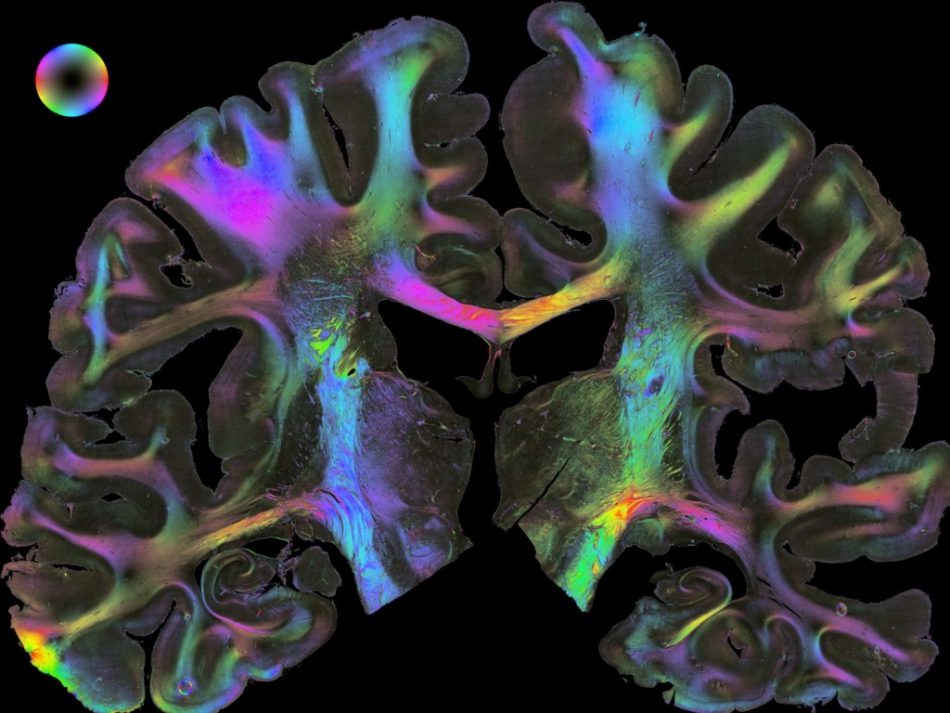

Ein dreidimensionaler Gehirnatlas sowie verschiedene Methoden der Hirnsimulation und Modellierung finden sich ebenfalls hier. Ein in Jülich speziell entwickeltes Verfahren, das mit polarisiertem Licht arbeitet, ist dadurch in der Lage, die hauchdünnen Nervenendigungen sichtbar zu machen. Bilder dieser bunt gefärbten Axone wurden auf große Poster gezogen.

Am Forschungszentrum Jülich kartieren Neurowissenschaftler gemeinsam mit Physikern und Ingenieuren die Hirnrinde und die darunter liegenden Kerngebiete. Sie erfassen und analysieren jede Zelle und sogar einzelne Moleküle, die für die Übertragung von Reizen und Informationen wichtig sind. Das tun sie anhand von Gewebeschnitten, die gerade einmal ein 20-Tausendstel Millimeter messen. Daraus ziehen die Forscher Rückschlüsse auf die Funktionsweise des Gehirns.